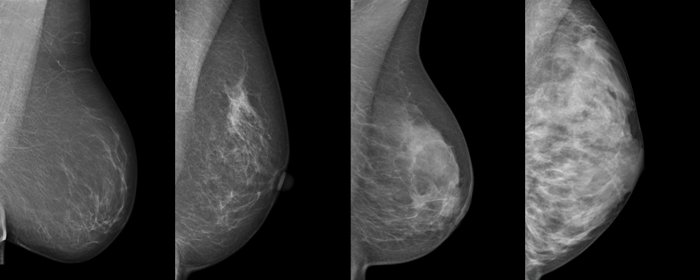

Die vier Dichtegrade der Brust in der Mammographie

Das folgende Bild zeigt typische Beispiele für die vier Brustdichtegrade in der Mammographie:

Die dichten, (in der Mammographie hellen) Bezirke entsprechen dabei Brustdrüsengewebe, während die dunklen, 'transparenten' Bezirke Fettgewebe entsprechen, da Fettgewebe für Röntgenstrahlen wesentlich 'durchsichtiger' ist als Drüsengewebe.